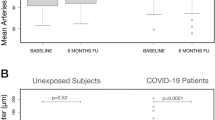

Coronavirus-related ischemic and hemorrhagic stroke

ACE2 has been shown to attenuate inflammation, thrombus formation and platelet aggregation [58, 71]; given that SARS-CoV-2 directly binds ACE2 in blood vessels, this is a likely source of microvascular dysfunction [40, 72, 73]. Loss of ability to prevent thrombosis likely occurs following cell entry of SARS-CoV-2 [72]. Several studies have associated SARS-CoV-2 infection with stroke and vasculopathy in both young and old patients [23, 24, 74,75,76,77,78,79]. The likelihood of ischemic stroke is eight times higher in patients with SARS-CoV-2, compared to influenza [80]. SARS-CoV-2 is associated with a prothrombotic state causing arterial and venous thromboembolism [81]. Patients have markedly elevated D-dimer, and consumption of fibrinogen. Abnormal coagulation markers have been associated with poor prognosis among patients with SARS-CoV-2 infection [81]. The exact mechanisms underpinning increased stroke rates remain to be further elucidated.